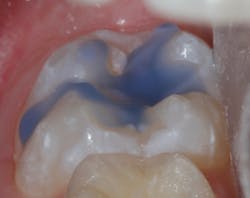

Sealant placement techniques should include complete isolation and an intermediary bonding layer (figure 1).25–29 The bonding layer and sealant curing can be one of two different methods: either placement and light-curing simultaneously in a simplified sealant technique or separately. Evidence-based studies show results favoring the individual light-curing technique in cases where conditions are dry and noncontaminated. In cases where there is saliva contamination, bond strength was the same in either simultaneous or individual light-cure placement methods.30–31